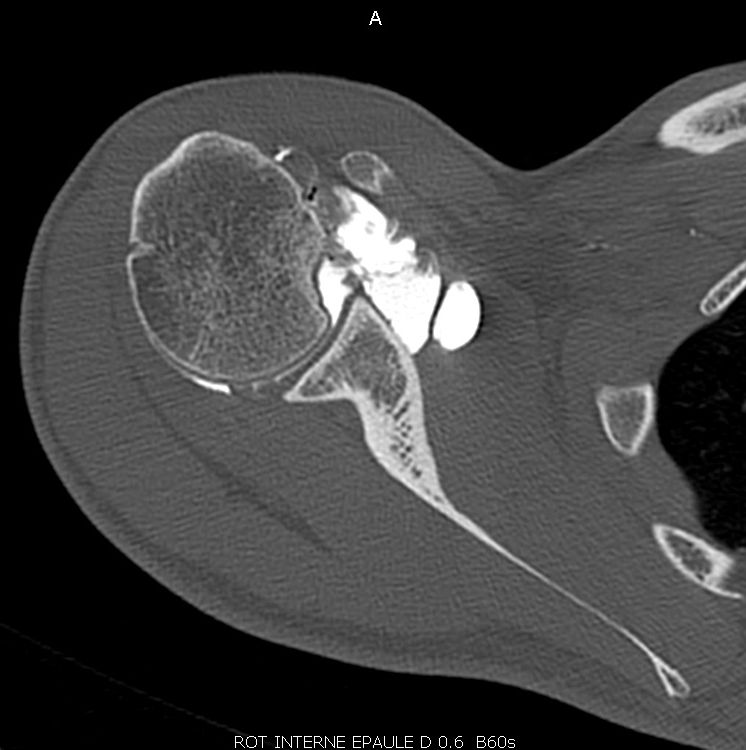

A CT scan is the best way to both analyse bone lesions and search for glenoid hypoplasia, dysplasia or retroversion as predisposing factors (Fig 1). Posterior labral damage on contrast-enhanced images may also indicate a labral fissure (Fig. 2). However, any such capsulolabral detachment is only pathological if located at the inferior, subequatorial portion of the bone.

Likewise, take time to check for any associated cartilage damage since this is a very important prognostic factor, as discussed below. For detecting soft tissue lesions and cartilage defects MR imaging is superior to CT and can also be done as Arthro-MRI.